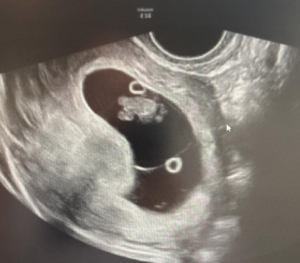

The ultrasound images demonstrated a single spinal column, two stomachs, and two hearts (Figure 2A). Two fused abdomens were observed, along with subcutaneous edema measuring 2.0 mm and 2.1 mm (Figure 2B). In addition, two pairs of moving legs were identified (Figure 2C). The trophoblast was located anteriorly, and a single corpus luteum was observed in the left ovary. Two follow-up examinations were required at 9 and 10 weeks of gestation to establish the diagnosis. At 9 weeks of gestation, the 3D ultrasound images lacked sufficient clarity for a definitive diagnosis (Figure 3). At 10 weeks of gestation, color Doppler imaging demonstrated two distinct cardiac activities, indicating the presence of two separate circulatory systems (Figure 4A). Three-dimensional imaging further revealed the face of one of the conjoined twins and confirmed the presence of two umbilical cords (Figure 4B).